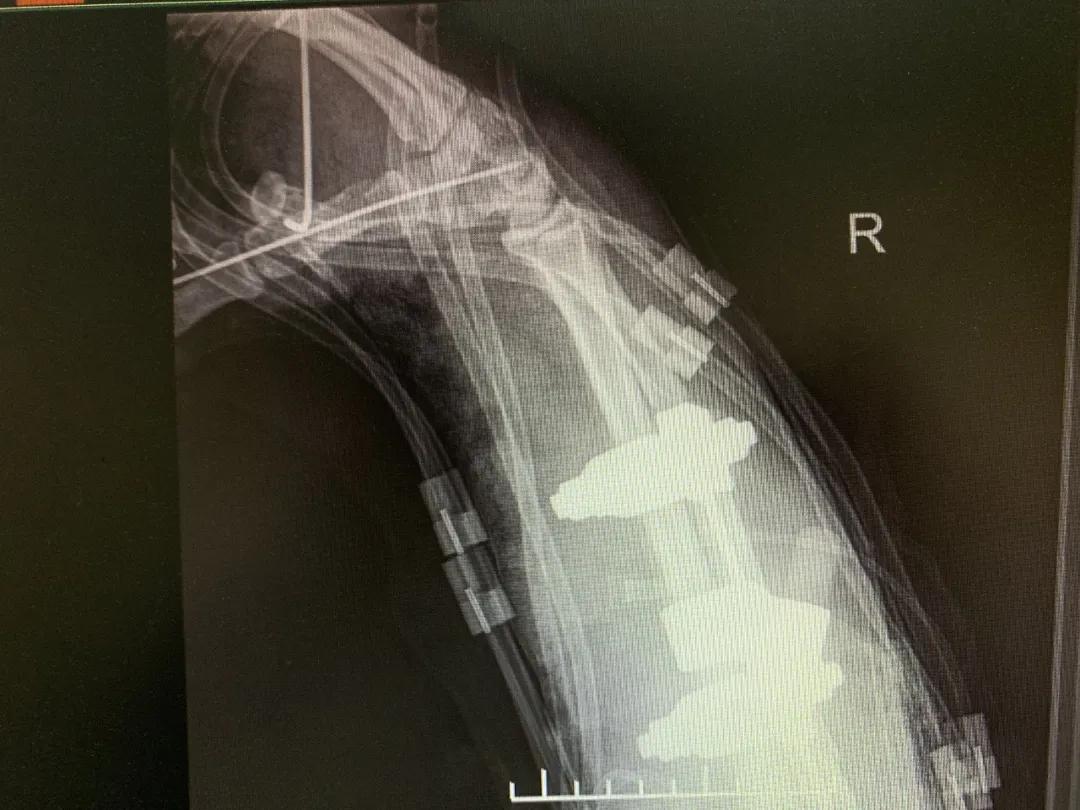

“正常的肢体都有皮肤保护着,如果没有皮肤,我们的肌肉、血管、神经、骨骼露在外面,都会发生坏死。”苑芳昌介绍,伤者的情况非常复杂,伴有多发骨折、肱骨骨折、骨关节的多发错位,还有腕部的骨折,更有血管、神经损伤。不仅如此,伤者右臂在机器里面受到绞伤,肌肉也已经大面积挫伤,各种复杂情形交织在一起甚至让手术“无从下手”。

清创、止血、接骨、将粉碎的骨块一块块拼接完整,同时给予VSD敷料负压引流。经过三次清创清除后,明确了坏死的皮肤等组织,创面好转,肉芽组织良好……

“前臂及手指血运缓缓流淌,肢体恢复血供,血运重建获得成功!”次日凌晨4时20分,患者被推出手术室。但是,几次清创后患者前臂皮肤出现大面积缺失,如不及时进行植皮覆盖修复手术,病人极有可能会继发感染,“极有可能造成前臂坏死肢体不保,那么前期所有的治疗和付出也就前功尽弃了。”